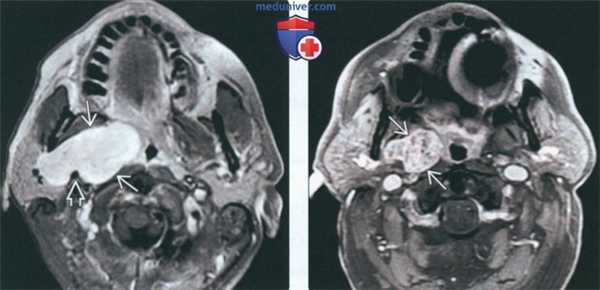

(Слева) На аксиальной МРТ (Т1ВИ С+ FS) в глубокой доле околоушной железы определяется большая опухоль с бугристыми краями, равномерно накапливающая контраст. Шиловидный отросток вдавливает задний край новообразования, что свидетельствует о нахождении опухоли (ДСО) в околоушном пространстве.

(Справа) На аксиальной МРТ (Т1ВИ С+ FS) в глубокой доле околоушной железы определяется опухоль неравномерно накапливающая контраст. Контрастирование ДСО варьирует: может быть равномерным, неравномерным, минимальным.